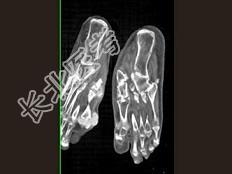

- 单项选择题男,55岁, 趾骨疼痛,皮肤红肿, 可触及结节,实验室检查高血尿酸, 结合图像,最可能的诊断是 ( )

C、痛风